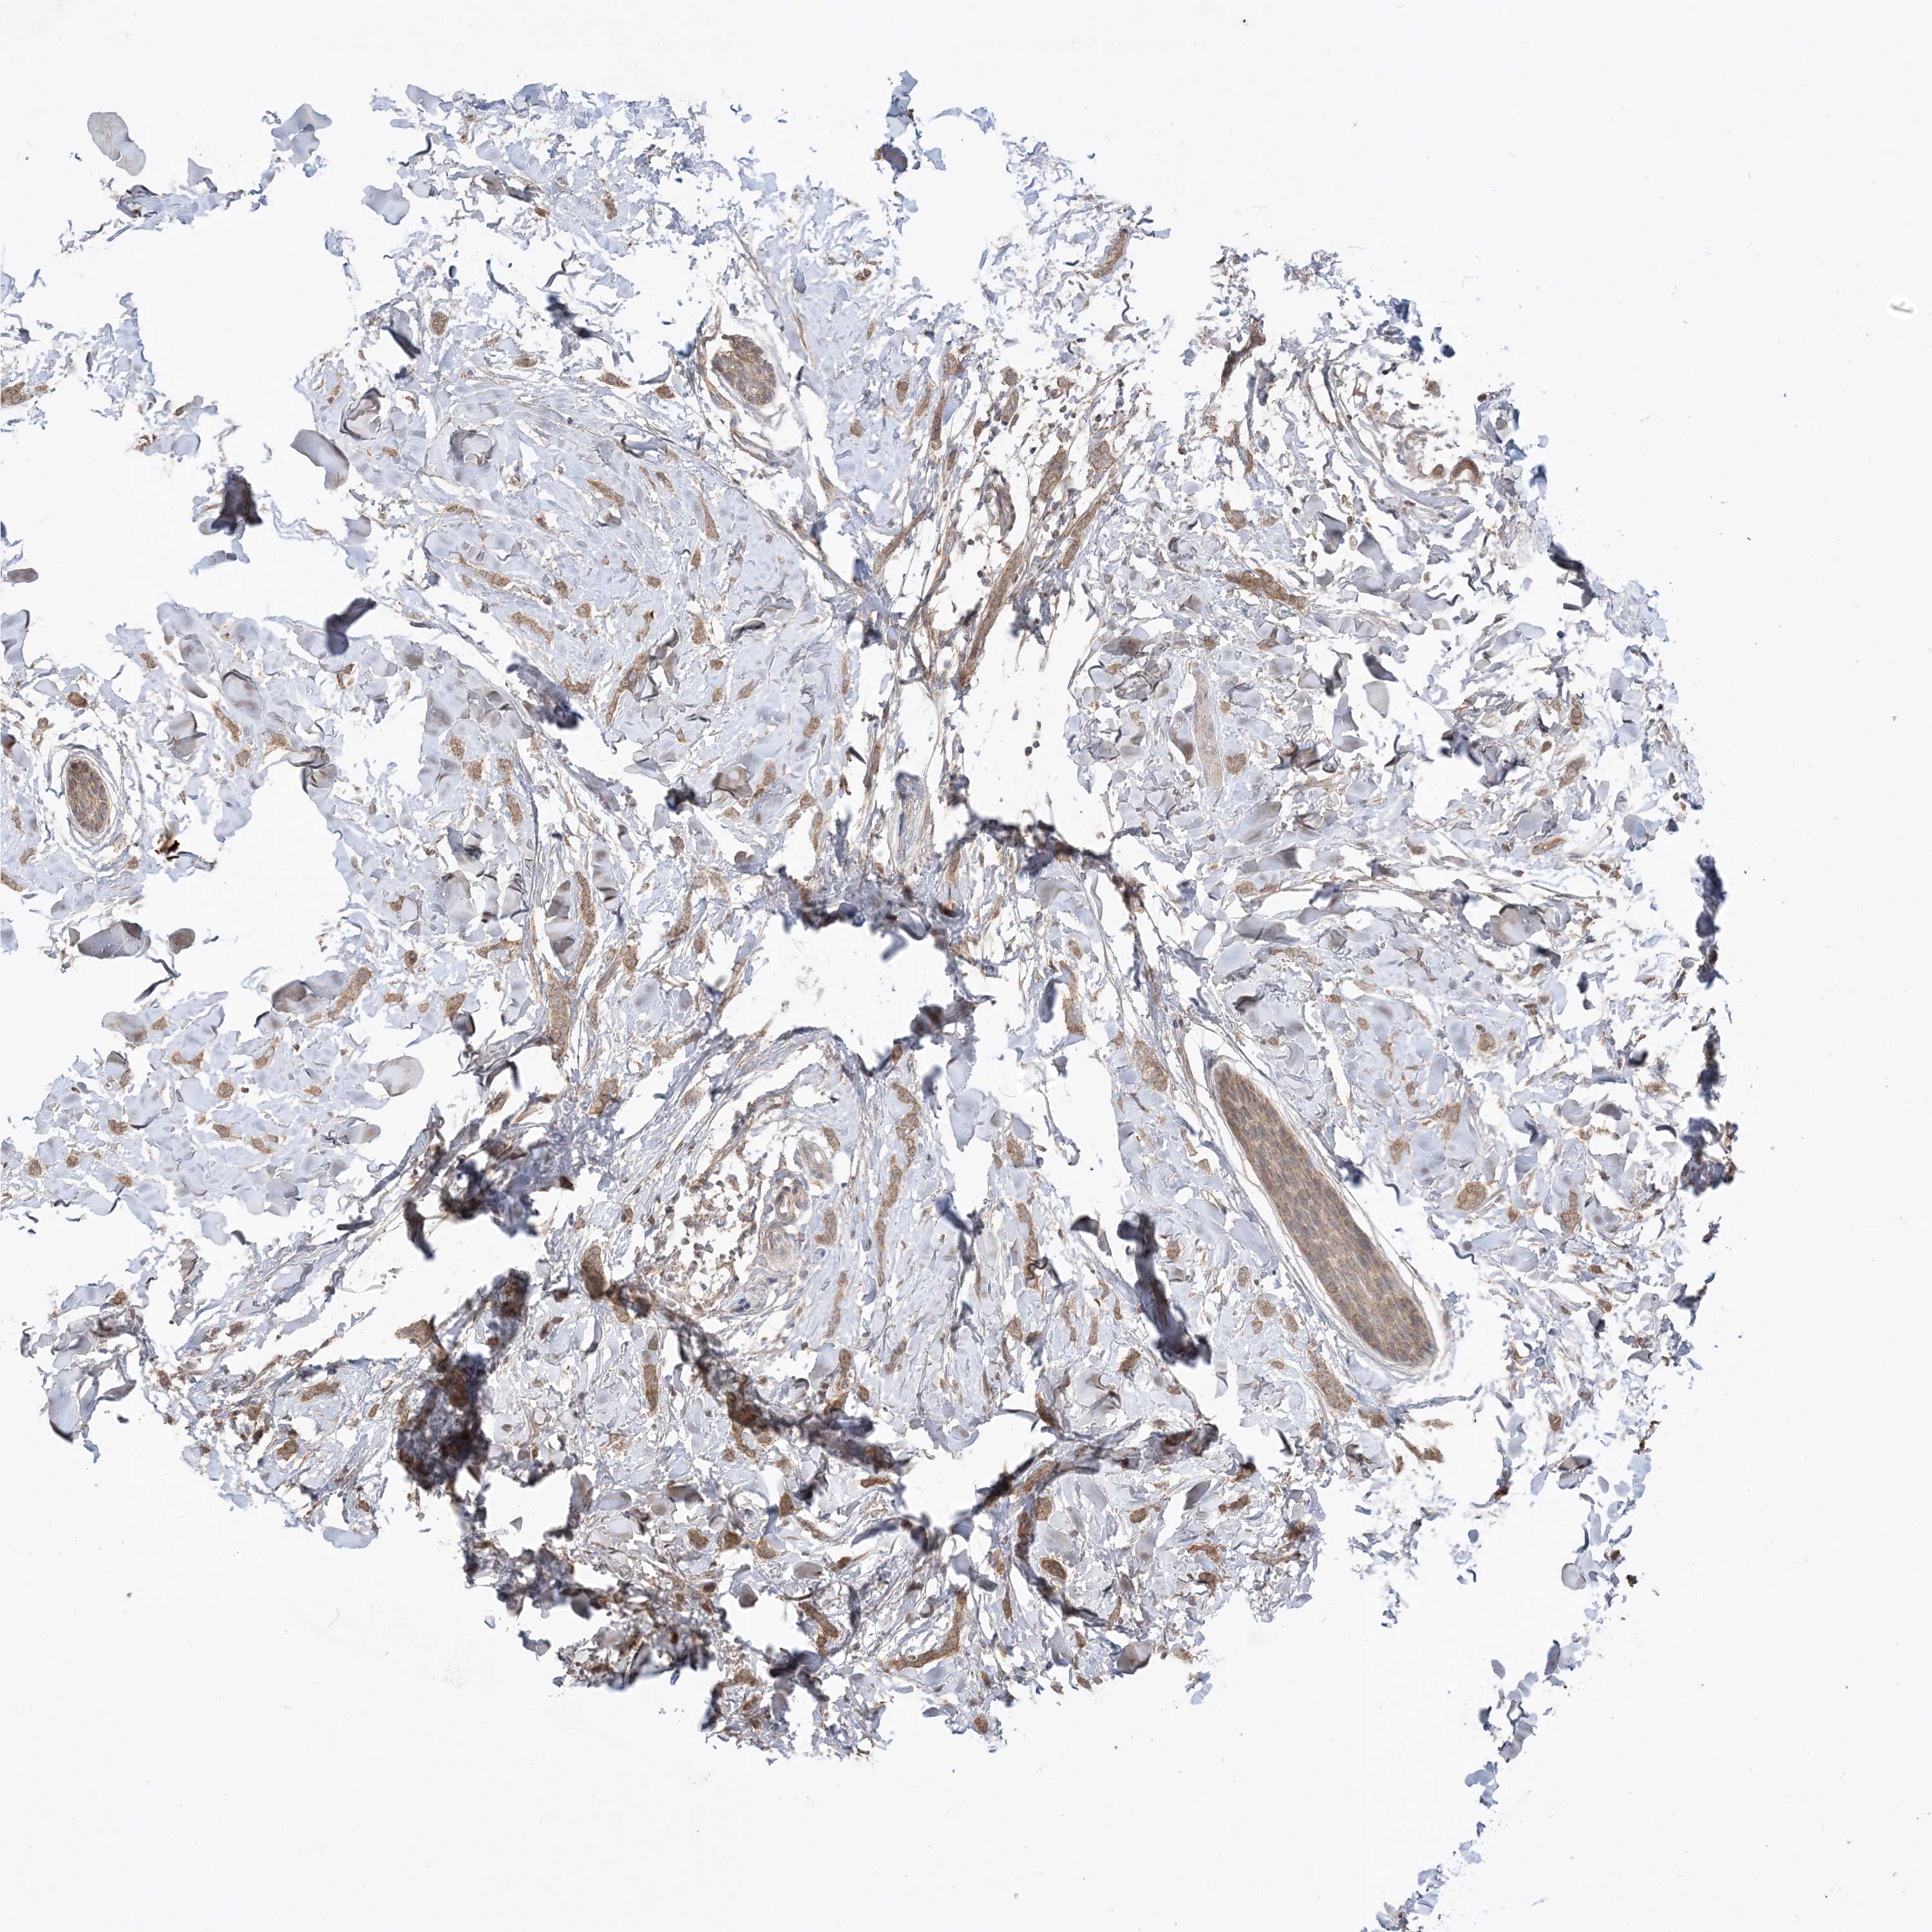

CANCER BREAST CANCER Show tissue menu

BRCA TCGA BRCA VALIDATION PROTEIN EXPRESSION